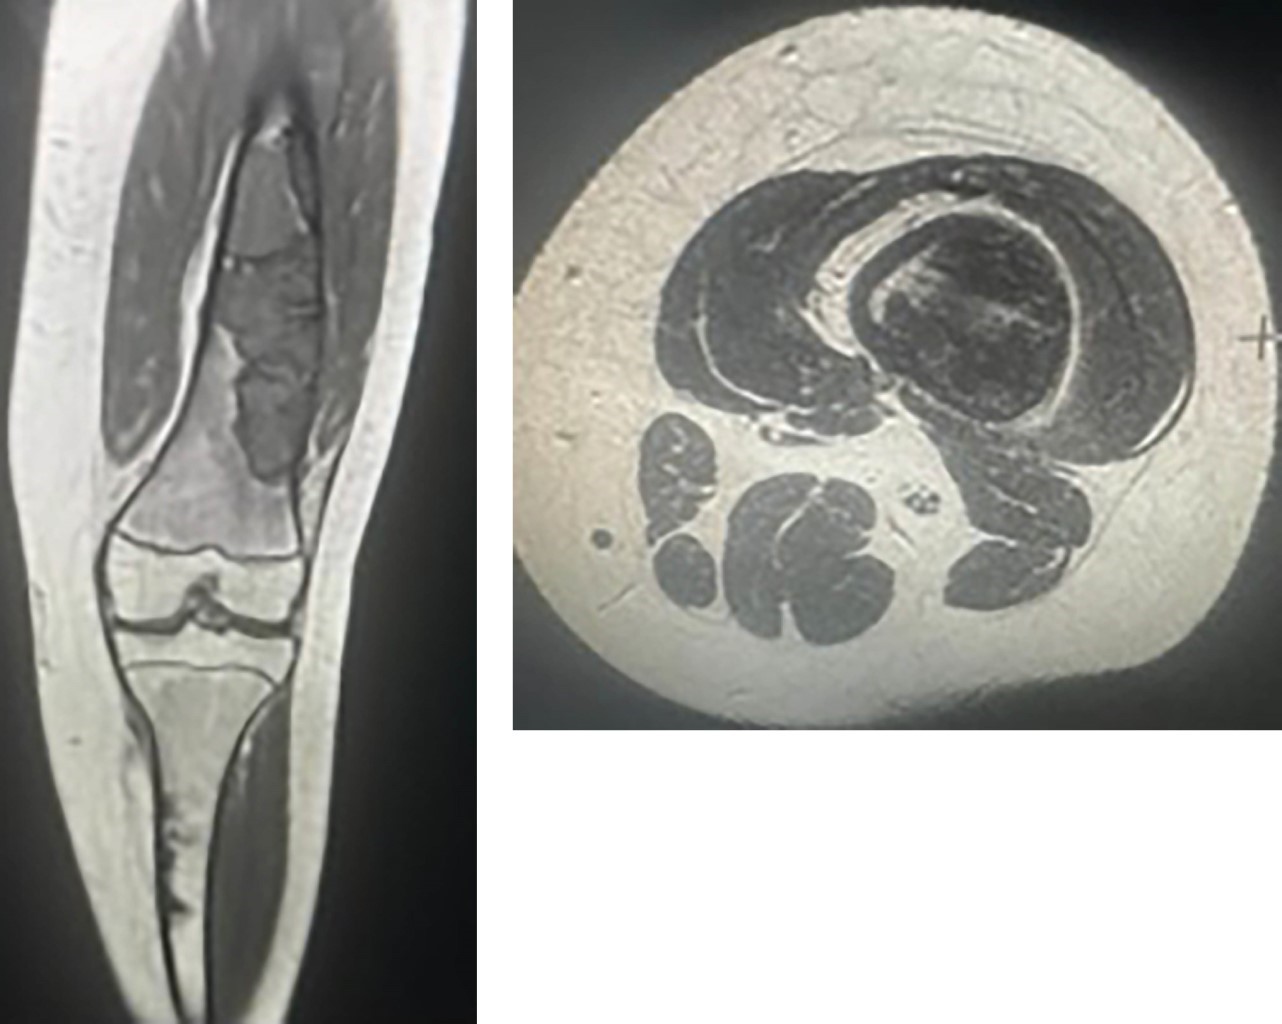

Se planifica cirugía de fémur distal derecho donde se realiza abordaje lateral de fémur distal derecho, se horada ventana cuadrada en región central de defecto principal, curetaje de la lesión, toma de tejido para biopsia y aseo con abundante suero fisiológico, luego se realiza curetaje a distal de la lesión completamente. Se rellena con 50 cm3 de aloinjerto óseo marca Sinermed (Providencia, Chile) en defecto metafisodiafisario, se determina el tamaño del istmo del canal medular y se introduce a nivel metafisodiafisario distal dos clavos TEN marca Synthes de 3.5 mm y uno de 2.5 mm contorneados con una curva de 45° en el extremo de inserción y una curvatura suave y uniforme sobre la longitud restante, entrelazadas entre sí en el canal medular, se comprueba adecuado relleno con injerto de la lesión y buena posición del hardware. Paciente permanece hospitalizada 72 horas postoperatorias con adecuada evolución y se da de alta con indicaciones de mantener la extremidad operada en descarga. Posteriormente asiste a control clínico, destacándose buena tolerancia al dolor con leve limitación a la flexoextensión, la radiografía de control postoperatorio muestra un adecuado posicionamiento de material de osteosíntesis y relleno óseo a nivel del defecto (Figura 4). Se inicia kinesioterapia y carga parcial. Al control radiológico se aprecian signos de consolidación en zona del injerto, por lo que se decide carga total a tolerancia y se controla al segundo mes de la cirugía, la paciente presenta mejoría en relación a marcha, mayor fuerza y rango articular de rodilla.

Figura 4